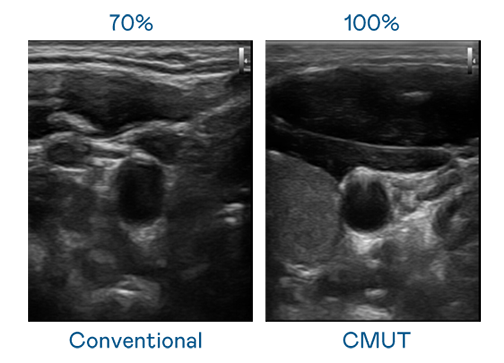

CMUT technology utilizes capacitive MEMS components to generate ultrasound signals. Compared to traditional ceramic piezoelectric technology, the 30% increased bandwidth of CMUT allows for wider ultrasound signals and greatly improved image resolution. This is a crucial technology for achieving medical ultrasounds with high-quality images and promoting the development of precision medicine.

Ultra-wide bandwidth offers high-quality images

The image quality of medical ultrasound depends on the signal bandwidth the ultrasound transducer can emit. AUO's CMUT offers high-resolution ultrasound signals with ultra-wide bandwidth and high sensitivity for more delicate image texture and details to help ultrasound medical examiners reduce time on interpreting and diagnosing based on precise medical images.